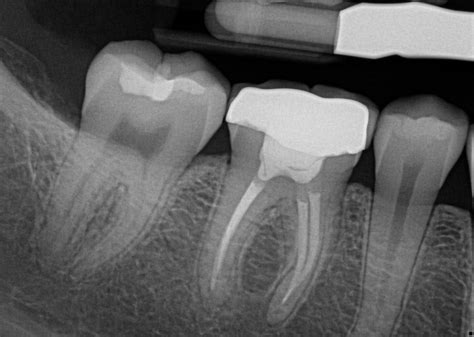

A dental X-ray reveals the severity of a tooth that requires a root canal, allowing for precise treatment and relief of pain.

When looking at an X-ray of a tooth that needs a root canal, your dentist will likely point out several things. Firstly, they'll identify the tooth in question, as well as any adjacent teeth. They'll also look for signs of infection or inflammation, such as a dark area around the root. This indicates the presence of bacteria, which can cause pain and discomfort.

Another thing your dentist will look for is the shape of the root canals. Ideally, they should be smooth and uniform in shape. However, in some cases, they may be curved or narrow, which can make the procedure more challenging. Your dentist may also look for any cracks or fractures in the tooth, which can affect the success of the root canal.

An x-ray of a tooth that needs root canal treatment will show signs of infection or damage to the tooth. The root canal may appear wider than normal, and there may be dark spots or shadows indicating an abscess or decay. The bone surrounding the tooth may also appear darker than normal, indicating the presence of infection or inflammation.

As I looked at the X-ray of this patient's tooth, I could see that there was a dark spot near the root. It was clear that this tooth needed a root canal. I could tell from the image that the tooth had already suffered significant damage, and if we didn't act soon, it would only get worse.